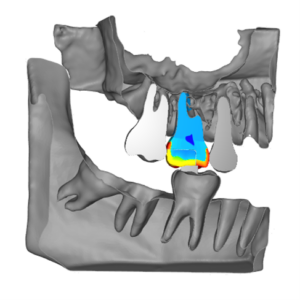

Distribution of elastic moduli (Young’s modulus) in a cross-sectional view (maxilla at the top and mandible at the bottom), showing the presence of a food bolus (a piece of food) between the two chewing teeth.